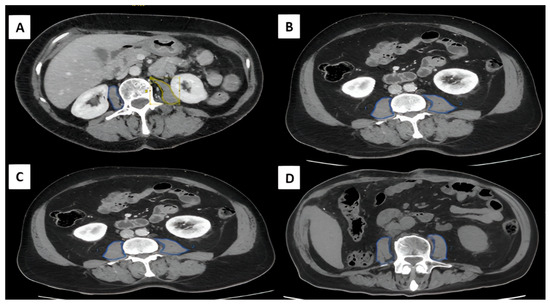

Objectives: Gastric cancer is one of the leading causes of cancer-related mortality. Sarcopenia, characterized by reduced skeletal muscle mass, strength, and physical performance, is associated with poorer outcomes in gastrointestinal cancers. This study aimed to evaluate the prevalence of sarcopenia, including the Total Psoas Area Index (TPAI), and its association with tumor stage, postoperative complications, and survival in patients with gastric adenocarcinoma. Methods: A retrospective study was conducted, including 79 patients who underwent surgery for gastric adenocarcinoma. Sarcopenia was assessed using a combination of CT-derived muscle mass (TPAI), muscle strength (dynamometry), and functional status (SARC-F). Patients were divided into sarcopenic (SG) and non-sarcopenic (NSG) groups. Clinical and survival data were compared between groups. Results: Sarcopenia was identified in 36.7% of patients. Early-stage disease (I–II) was less frequent in the SG (20.7%) compared to the NSG (44%), whereas stage IV tumors were more common in the SG (20.7% vs. 6%). Sarcopenic patients had a lower body mass index and underwent fewer laparoscopic procedures (44.8% vs. 68%, p = 0.03). Postoperative complications, such as pneumonia and ileus, were more frequent in the SG. Overall survival was significantly lower in the SG (17 vs. 21 months, respectively, p = 0.042), with a reduction in disease-free survival as well. Postoperative TPAI values remained lower in the SG. Conclusions: Sarcopenia, as defined by combined assessment including TPAI, was associated with advanced tumor stage, increased postoperative risk, and reduced survival in patients with gastric cancer. Preoperative assessment of muscle mass may help identify high-risk patients and optimize clinical management. Full article

Show Figures

Figure 1